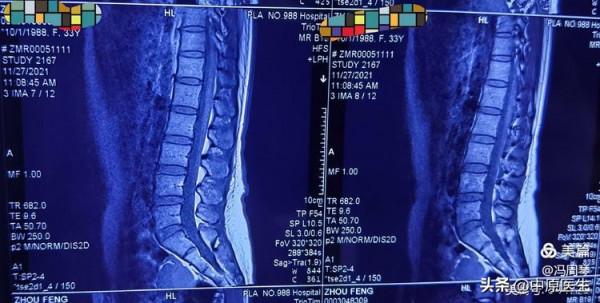

我為病人申請了頸胸段脊髓磁共振檢查,結果發現上胸段脊髓佔位病變。

頸胸段脊髓磁共振發現 T1~T2椎間盤水平椎管內佔位病變

找到了病變,抓住了元兇

(某解放軍醫院脊髓磁共振報告)

(北京天壇醫院脊髓磁共振報告)